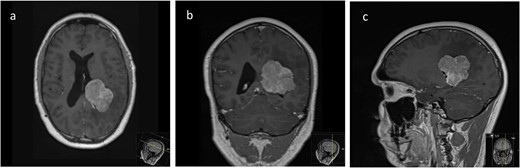

We hereby present the case of a 32-year-old gentleman referred to the neuro-oncology service with an 8-months history of left sided headaches, dizziness, and blurred vision. MRI head demonstrated a 50 × 52 × 51 mm lesion in the posterior horn of the left lateral ventricle, with extension into the periventricular white matter (Fig. 1). Following multi-disciplinary discussion, a plan was made for the patient to undergo a minimally invasive approach for resection of this lesion. Pre-operative cortical and subcortical mapping was performed with navigated transcranial magnetic stimulation (nTMS) and diffusion tensor imaging (DTI). The best trajectory was defined taking into consideration the localization of the cortico-spinal tract (CST, red), the inferior fronto-occipital fasciculus (IFOF, green) and the optic radiations (OR, yellow) (Fig. 2).

Lateral (a), ¾ lateral (b), and posterior (c) views of the pre-operative virtual 3D reconstruction model. The tumour (purple) is reached by the tubular retractor (white) and encircled by the associated white matter tracts: the CST (red) superiorly and anteriorly, and the IFOF (green) and the OR (yellow) that are located inferiorly, laterally, and posteriorly to the lesion.